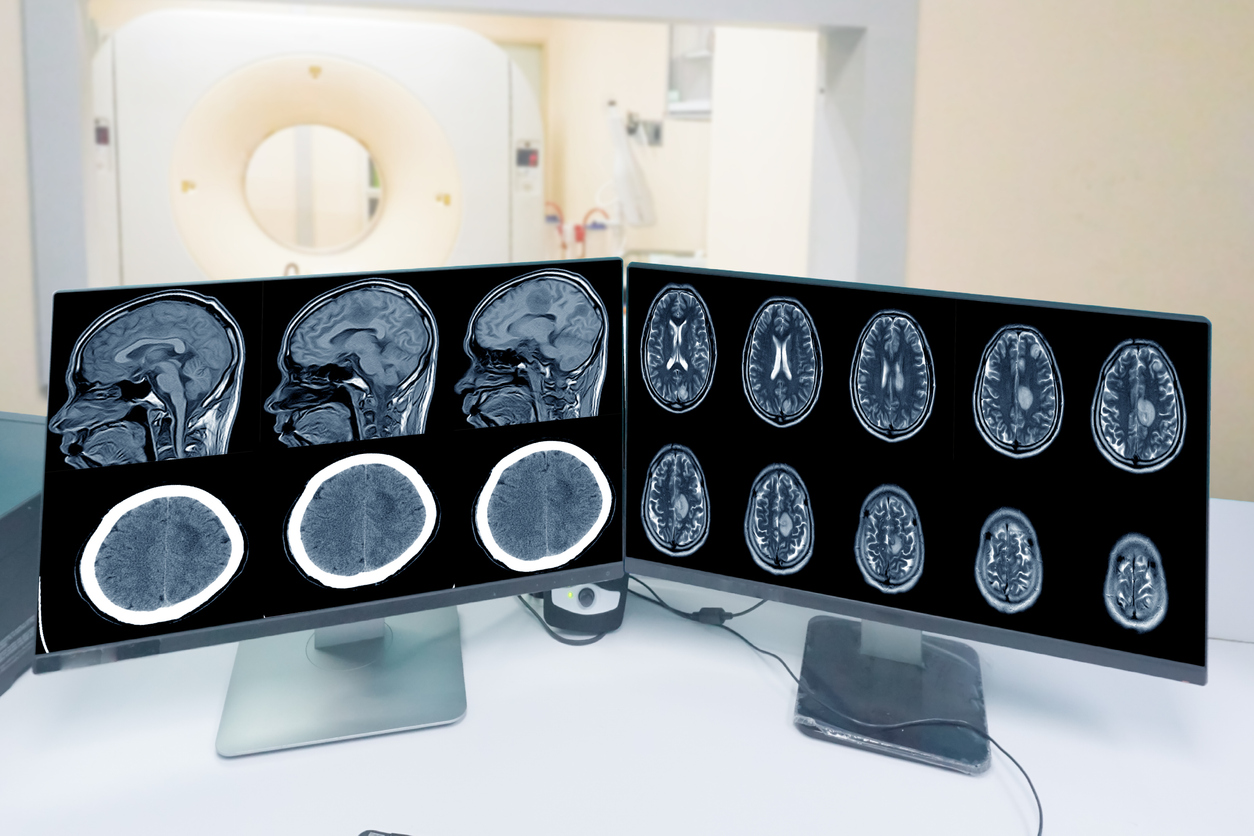

Η ατμοσφαιρική ρύπανση συνδέεται με κοινούς όγκους του εγκεφάλου

Οι άνθρωποι που εισπνέουν περισσότερη ατμοσφαιρική ρύπανση έχουν υψηλότερο κίνδυνο να αναπτύξουν έναν κοινό μη καρκινικό όγκο στον εγκέφαλο, σύμφωνα με νέα μελέτη.

Αρκετοί διαφορετικοί τύποι ατμοσφαιρικών ρύπων, συμπεριλαμβανομένης της σωματιδιακής ρύπανσης και του διοξειδίου του αζώτου, φαίνεται να αυξάνουν τον κίνδυνο εμφάνισης μηνιγγιωμάτων – όγκων που σχηματίζονται στα στρώματα του ιστού που καλύπτουν τον εγκέφαλο και τον νωτιαίο μυελό, ανέφεραν οι ερευνητές στις 9 Ιουλίου στο περιοδικό Neurology.